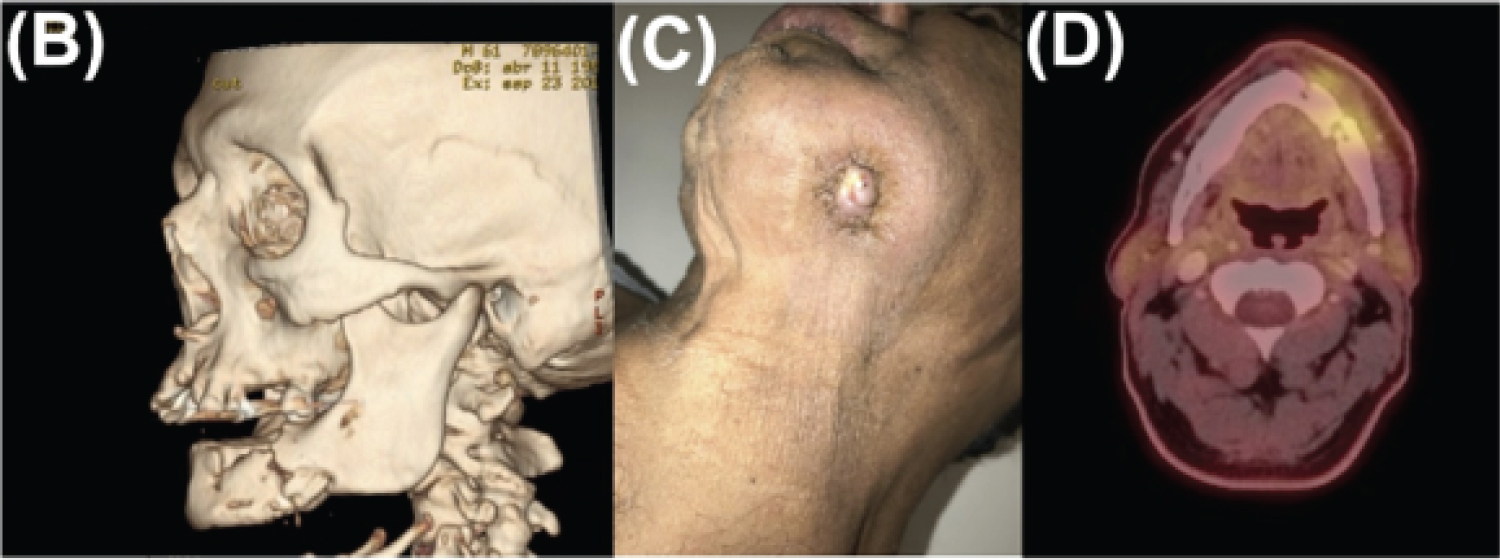

The extraoral examination revealed a volume increase and a cutaneous fistula with purulent drainage in the left submandibular area. On intraoral examination, an upper partial edentulism with multiple cervical caries, and a mandibular edentulism with an increase in volume in the left alveolar ridge, with bone exposure in the tooth area 3.6. Also, a 3 mm mobile bone sequestration was observed in the lower lingual area, and a vestibular bone exposure of 2 mm. The patient was hospitalized for decompensated IRDM and intravenous antibiotic therapy with Ceftriaxone 2 gr/day and Clindamycin 600 mg every 8 hours. An Orthopantomography (OPG) was requested, which revealed diffuse radiolucent areas compatible with pathological mandibular fracture and basilar bone sequestration (Figure 1). A computerized axial tomography (CT) revealed diffuse hypo and hyperdense areas with destruction processes and multiple bone sequestration that reached the basilar border. Besides confirming ORN diagnosis and ruling out tumor recurrence at the affected site, a positron emission tomography (PET-CT) was requested, which showed isolated bone fragments compatible with sequestration and bone metabolic hyperactivity suggestive of osteomyelitis, confirming the diagnosis of ORN Notani stage III (Supplementary Figure 1B, Supplementary Figure 1C and Supplementary Figure 1D). An angio-CT of inferior extremities was requested to evaluate the eventual mandibular reconstruction with fibula free flap. The images showed advanced multiple atheromatosis, which within the context of the multiple comorbidities of the patient contraindicated this procedure.

Supplementary Figure 1: B) CT-Scan showing a pathological fracture in the left mandibular body, with the presence of multiple bone sequestration; C) Active orocutaneous fistula in the skin of the left submandibular region associated with refractory ORN and D) PET-CT with areas of mandibular bone metabolic hyperactivity. View Supplementary Figure 1